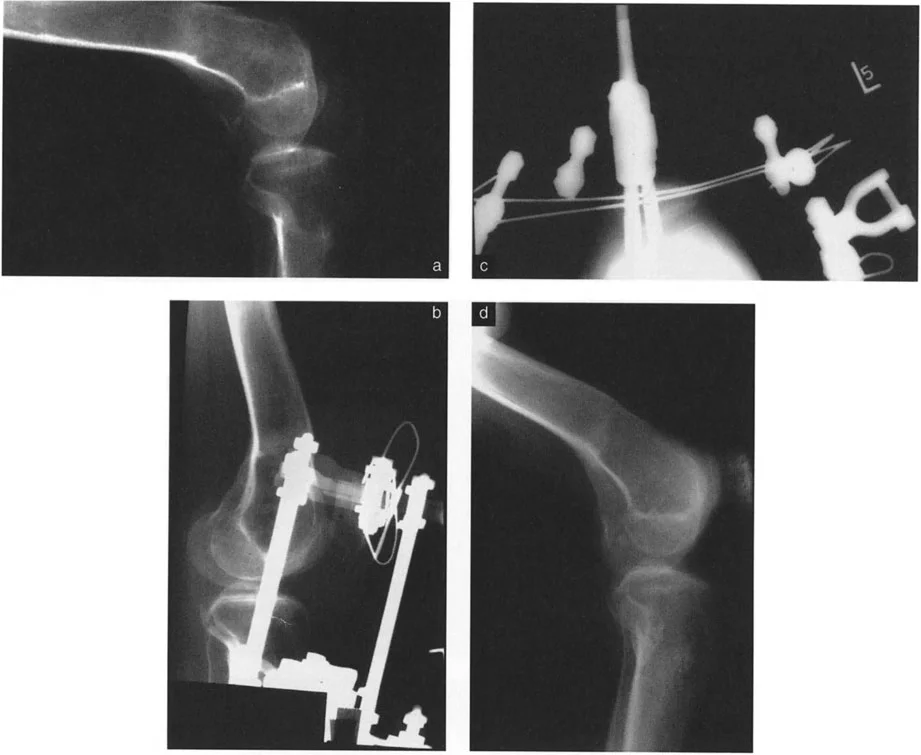

تُظهر الصورة تشوه التقوس الأمامي في عظم الفخذ وكيف يؤثر على محاذاة الركبة، مما يستدعي تدخلاً جراحياً دقيقاً.

تُظهر الصورة تقنية قطع العظم فوق الحدبة الظنبوبية، حيث يتم تصحيح التشوه وسحب الحدبة الظنبوبية للأمام لتقليل الخلع الجزئي الخلفي.

تُظهر الصورة تخطيطاً لقطع العظم على شكل حرف L، وهي تقنية معقدة تستخدم لتصحيح التقوس الخلفي بعد كسور هضبة الظنبوب.

تُظهر هذه الصورة نتائج جراحة قطع العظم على شكل حرف L، مع استعادة المحاذاة التشريحية للركبة.

تُوضح الصورة كيفية تصحيح التقوس الخلفي الناتج عن العلاج الإشعاعي باستخدام جهاز إليزاروف، مما يحقق محاذاة طبيعية للركبة.